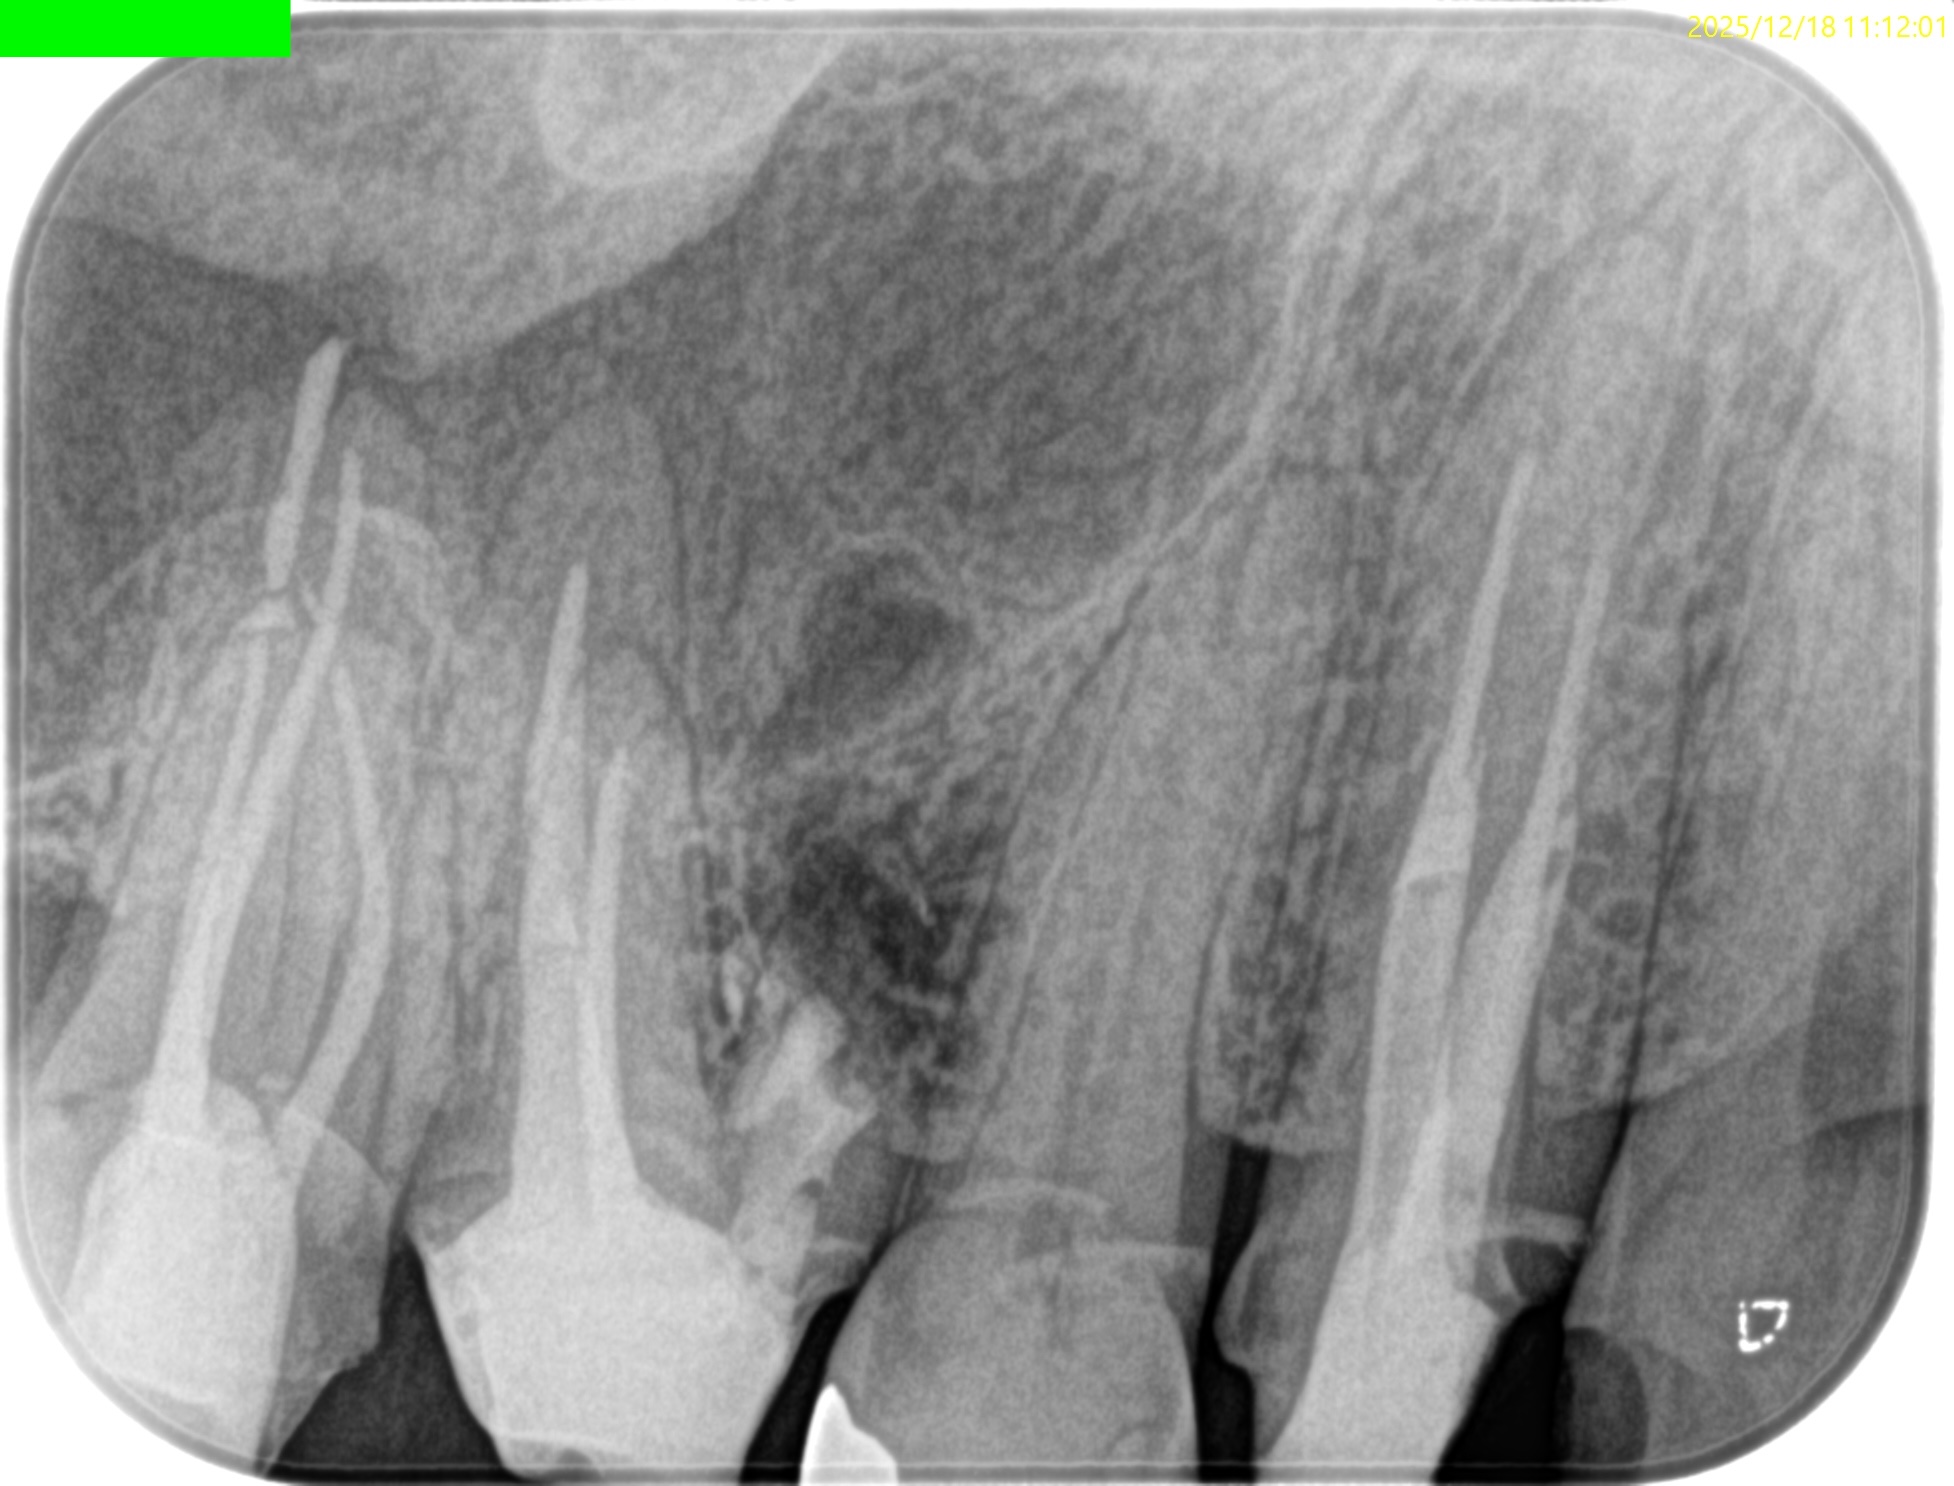

紹介患者さんの治療で、#3 MB Apicoectomyを行ったのだが

MBをRoot resectionした。

ここまでは容易なのだが、この後に逆根管形成・逆根管充填を行うが、

明後日の方向に逆根管形成・逆根管充填してしまう

この状態ではMB2の封鎖がままならない。

つまり、やり直しが必要だ。

その際は、この穿孔部を消去したいので

さらに切断部位から4mm, 頬舌的幅径が6.7mm必要だが再切断し逆根管形成・充填を試みることにした。